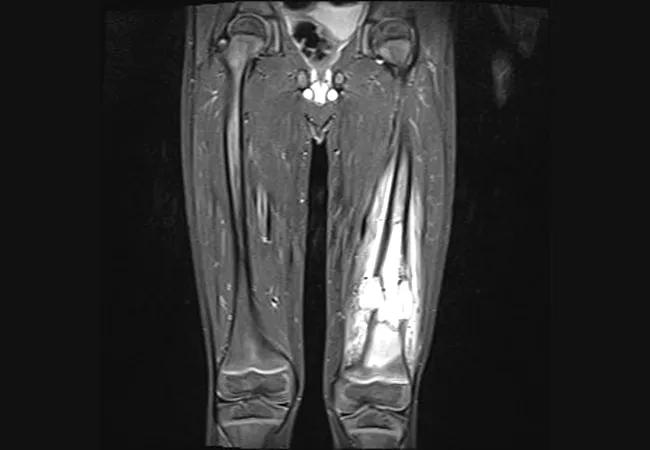

Osteosarcoma in the 4-year-old patient’s left knee.

In September 2014, a 4-year-old boy with pain in his left knee was referred by his pediatrician to Cleveland Clinic’s Musculoskeletal Tumor Center/Pediatric Oncology where physicians diagnosed a high-grade osteosarcoma in the distal femur. Neoadjuvant chemotherapy was provided. The patient received 10 weeks of a multi-drug regimen that included Methotrexate and Adriamycin. Study of the en bloc resected specimen after initial chemotherapy showed necrosis of 90 percent of the tumor cells.